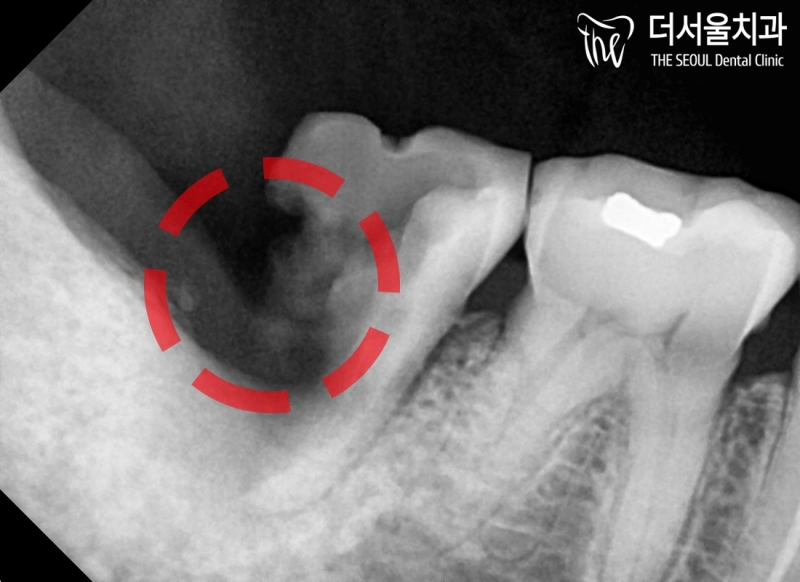

반갑습니다. 태평동 더서울 치과 입니다. 많은 분께서 이런 생각을 가지고 있으실 겁니다. ‘잇몸뼈 문제로 치아가 떨어졌다면, 임플란트 심는게